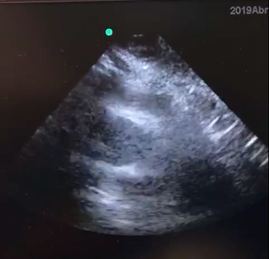

As the patient improved with hydration, the decision is made to release him. After this, the patient’s upper extremities begin to move rigidly, and his eyes deviate to the left side. The patient then states he feels dizzy and weak overall, he looks pale and then presents persistent hypotension, extreme bradycardia, distal coldness and desaturation. Ultrasound tracing of the subxiphoid window was performed with ultrasound imaging within the ventricles. Thrombolysis is begun using a recombinant tissue plasmogen activator 100mg IV over 2hours. After this is started, the patient goes into pulseless electrical activity cardiac arrest. Cerebral pulmonary reanimation maneuvers are performed. Bicarbonate (7 direct ampoules) is used, and the dose of the recombinant tissue plasmogen activator thrombolytic agent changed to 50mg via bolus. After 35minutes of reanimation, the patient regains spontaneous circulation with a sinus rhythm and hemodynamic instability. Perfusion is begun with 10 mcg/min of Adrenaline and 20mcg/kg/min of Dobutamine. Assisted mechanical ventilation is continued without sedation and analgesia. He is transferred for an angiotomography of the pulmonary vessels where acute thrombi are identified in the main pulmonary arteries on both sides and in the segmental branches in the upper and lower lobes.

Figure 1A Alterations in the size of the right ventricle, decreasing compared to the left ventricle.

Figure 1B Deviated septum.

During emergency care for this patient no CT confirmation could be performed due to rapid clinical instability, the need to secure his airways, and the early start of reanimation maneuvers. For this reason, a bedside ultrasound is performed on the patient, seeking signs of pulmonary embolism, including free intracavitary thrombi or thrombi in the pulmonary artery (as presented in this patient), or indirect signs like dilation of the Right Ventricle vs the Left Ventricle (>1:1 RV/LV), systolic disfunction of the right ventricle, septum displacement in the left ventricle, inferior vena cava (IVC) without collapse, or evidence of DVT in the lower extremities17–19 McConnell’s sign is the most sensitive and specific indirect sign: hypokinetic free wall of the right ventricle in the four-chamber projection; with an original described sensitivity of 77% and a specificity of 94%, although there are other studies that speak of a low specificity of 33 to 40%.20